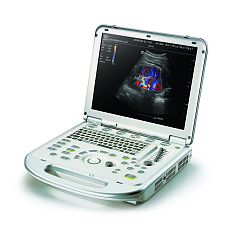

УЗИ аппарат Chison SonoTouch 80 Pro

Характеристики УЗИ аппарат Chison SonoTouch 80 Pro

Переносной ультразвуковой сканер Chison Sonotouch 80 Pro применим для различных сфер - акушерства, гинекологии, урологии, ангиологии, маммологии, кардиологии, ортопедии, педиатрии, неонатологии, ветеринарии, биопсии и т.д. Аппарат выполнен в форме ноутбука с весом до 5.5 кг. Эргономичная панель управления позволяет добраться практически до любой функции за одно нажатие и имеет функцию автоподстройки подсветки в зависимости от окружающего освещения. Sonotouch 80 Pro оснащен бесштырьковым портом для подключения легковесных ультразвуковых датчиков одним движением.